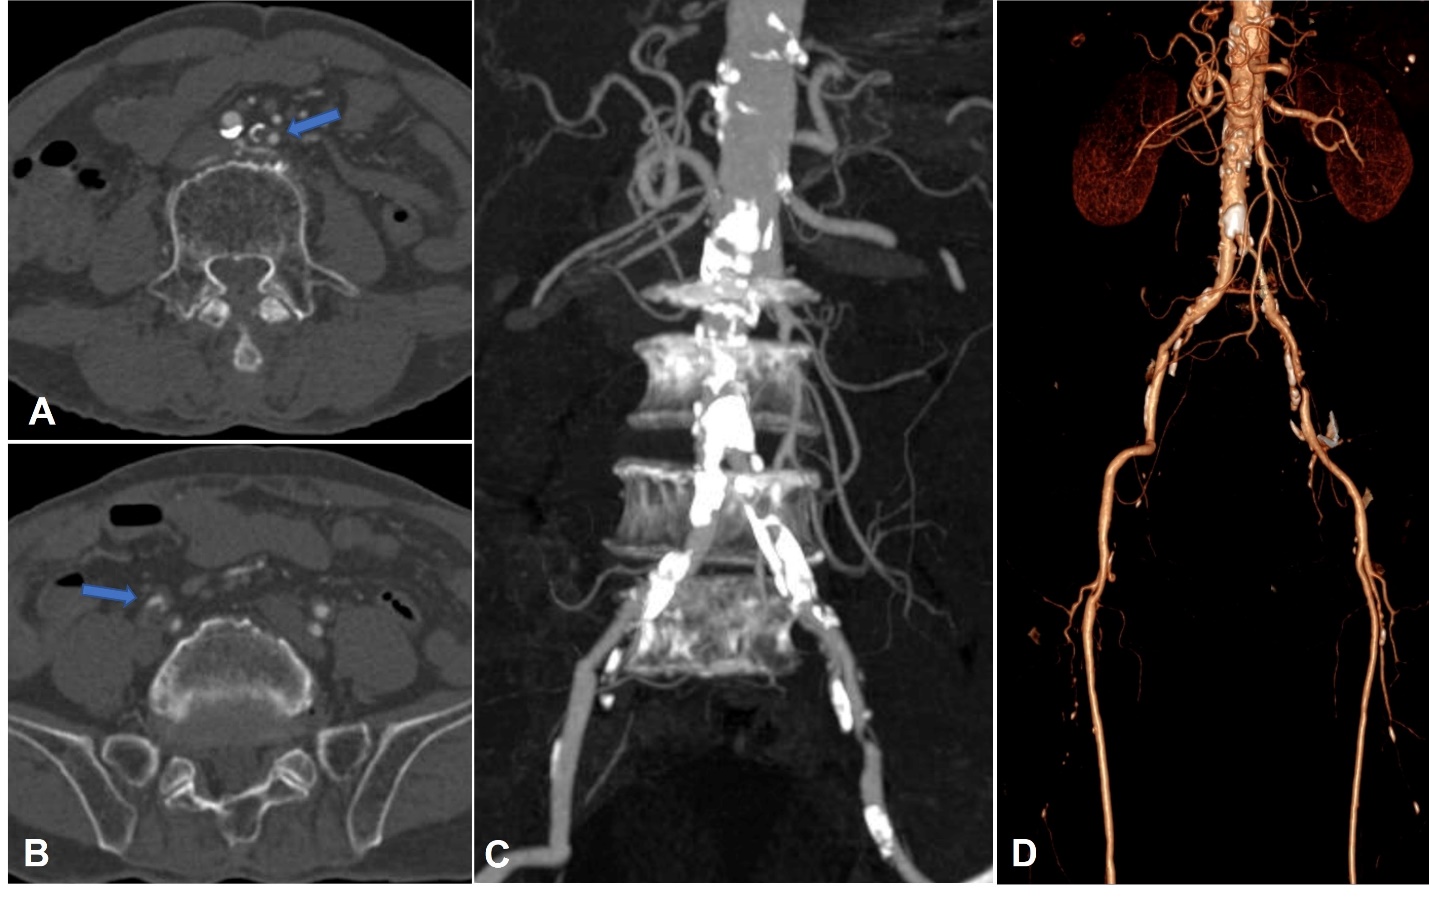

Bệnh nhân nam 77 tuổi, tiền sử ung thư trực tràng đã đã phẫu thuật, đang điều trị hoá chất, vào viện vì triệu chứng đau hai chân, đi lại khó khăn. Thăm khám lúc vào viện ghi nhận bệnh nhân tỉnh táo, sinh hiệu ổn (mạch 60 lần/phút, huyết áp 130/80 mmHg), đau kèm tê hai chân, không thấy sưng nóng đỏ, có đau cách hồi rõ, mạch đùi còn bắt rõ, mạch mu chân không bắt được, không thấy loét hay hoại tử khô đặc biệt ở các ngón. CT toàn thân cho thấy tổn thương thứ phát đa ổ trên nền tổn thương viêm xơ giãn phế quản khắp hai phổi, chưa thấy tổn thương nghi tái phát hay thứ phát trong ổ bụng. Trên CLVT mạch máu (CT angiography) thấy xơ vữa vôi hoá lan toả động mạch chủ bụng và động mạch chậu hai bên, gây hẹp nặng khẩu kính động mạch chậu chung hai bên #90% (Hình 1). Tổn thương xơ vữa lan đến động mạch chậu trong, chậu ngoài hai bên và các nhánh. Xơ vữa vôi hoá gây hẹp từng đoạn hệ động mạch chi dưới nhiều mức độ, khoảng 50-70%. Chưa thấy tổn thương thâm nhiễm, loét mô mềm chi dưới hai bên.

Hình 1. Hình ảnh cắt lớp vi tính mạch máu (CTA) mặt phẳng axial (A, B), tái tạo MIP (C) và VRT (D): Tổn thương xơ vữa vôi hoá lan rộng ở đoạn cuối động mạch chủ bụng, động mạch chậu chung, chậu trong, chậu ngoài hai bên, gây hẹp nặng khẩu kính (mũi tên).

Ở bệnh nhân này, trên CTA thấy tổn thương xơ vữa vôi hoá lan rộng và hẹp nhiều vị trí ở đoạn cuối động mạch chủ, động mạch chậu chung, chậu ngoài, chậu trong hai bên, được phân loại TASC D, tổn thương kéo dài >4cm, vôi hoá chiếm >50% tổn thương và bao quanh lòng mạch >180 độ nên được phân loại tổn thương lan toả, vôi hoá nặng. Bệnh nhân được chỉ định can thiệp nội mạch sau khi hội chẩn đa chuyên khoa. Trong trường hợp này, giải quyết chỗ hẹp bằng stent nở bằng bóng (balloon expandable stent) được xem là tối ưu. Tuy nhiên, trong điều kiện hiện tại không có sẵn loại stent này, chúng tôi quyết định sử dụng stent kim loại đơn thuần (mức độ khuyến cáo vừa-mạnh). Kỹ thuật được chọn là kissing stent, tức là hai stent được thả đồng thời để đảm bảo dòng chảy cân bằng cho cả hai bên, tránh tình trạng một stent nở ưu thế gây chèn ép dòng chảy bên đối diện. Sau khi thả stent, chúng tôi nong lại đồng thời trong stent để tối ưu hoá khẩu kính động mạch. Chụp kiểm tra sau stent thấy dòng chảy lưu thông tốt, tốc độ cao, không thấy hẹp.